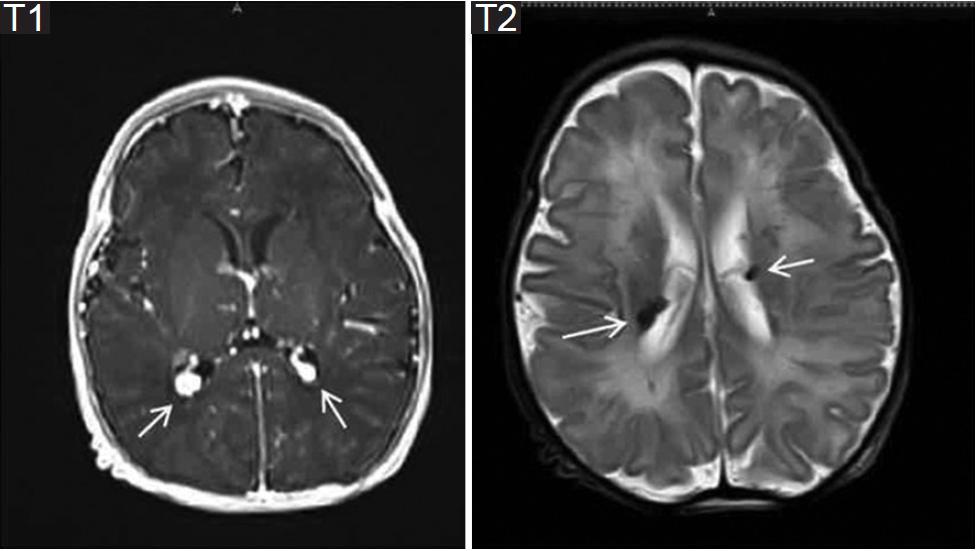

- El primer caso se trata de una paciente de 20 años de edad, sin antecedentes heredofamiliares de importancia, la cual inicia control de embarazo de alto riesgo en tercer nivel por múltiples amenazas de aborto. Derivada a nuestro hospital a las 36 semanas de gestación, realizándose el primer ecocardiograma prenatal por parte de nuestro servicio detectando tumores cardiacos compatibles con rabdomiomas, con imagen ecogénica en aurícula derecha de 18 mm y en ventrículo derecho de 20 mm con septum interventricular de 8 mm (Fig. 1), sin datos de obstrucción al tracto de salida, por lo que se decide continuar con el embarazo. Nace por cesárea, sin complicaciones. Se realiza ecocardiograma posnatal de control con los hallazgos previos, reportando tumoración a nivel de la cava superior de 13 x 18 mm, tumoración en surco atrioventricular de 15.4 x 4.5 mm, en ventrículo derecho con tumoración de 17.4 x 22 mm, siendo bilobulado, a nivel del ventrículo izquierdo con múltiples tumoraciones adheridas al septum y a la pared anterior la mayor de 7.7 x 8.2 mm (Fig. 2), corroboradas por resonancia magnética (Fig. 3). Debido a la asociación de tumores intracardiacos con esclerosis tuberosa fue valorado por el Servicio de Neurología, en donde mediante la realización de resonancia magnética de encéfalo se evidencia lesión nodular intraaxial en el giro recto derecho y nódulos subependimarios en ambos ventrículos laterales (Fig. 4), con hallazgos referidos que se encuentran dentro del espectro de esclerosis tuberosa. Se mantiene en vigilancia, en control por la consulta externa de dicho servicio.

Figura 4 Resonancia magnética de encéfalo, donde se observan múltiples lesiones nodulares periventriculares y subependimarias bilaterales con una intensidad de señal predominantemente alta en T1 y baja a intermedia en T2.